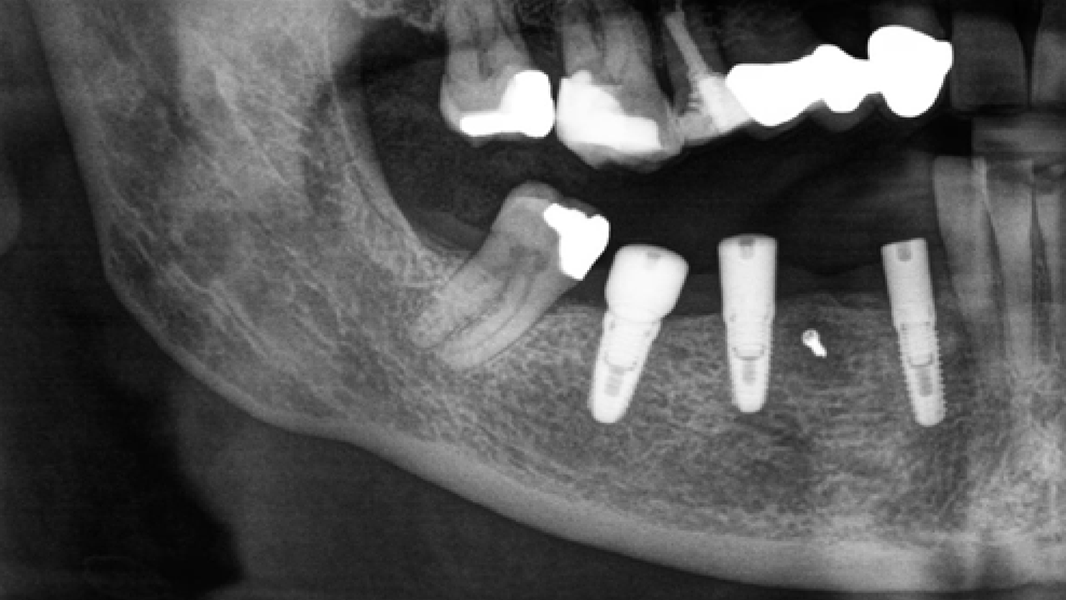

3 Kloss et al. Clin Case Rep. 2020, 8(5):886-893.

5 Kloss et al. Clin Oral Implants Res. 2018, 29, 1163.